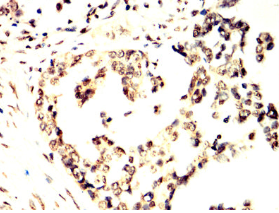

TCF7 Mouse Monoclonal antibody[1B4E9]

TCF-1

This gene encodes a member of the T-cell factor/lymphoid enhancer-binding factor family of high mobility group (HMG) box transcriptional activators. This gene is expressed predominantly in T-cells and plays a critical role in natural killer cell and innate lymphoid cell development. The encoded protein forms a complex with beta-catenin and activates transcription through a Wnt/beta-catenin signaling pathway. Mice with a knockout of this gene are viable and fertile, but display a block in T-lymphocyte differentiation. Alternative splicing results in multiple transcript variants. Naturally-occurring isoforms lacking the N-terminal beta-catenin interaction domain may act as dominant negative regulators of Wnt signaling.

Immunogen:    Purified recombinant fragment of human TCF7 (AA: 168-358) expressed in E. Coli.

IHC    1/200 - 1/1000